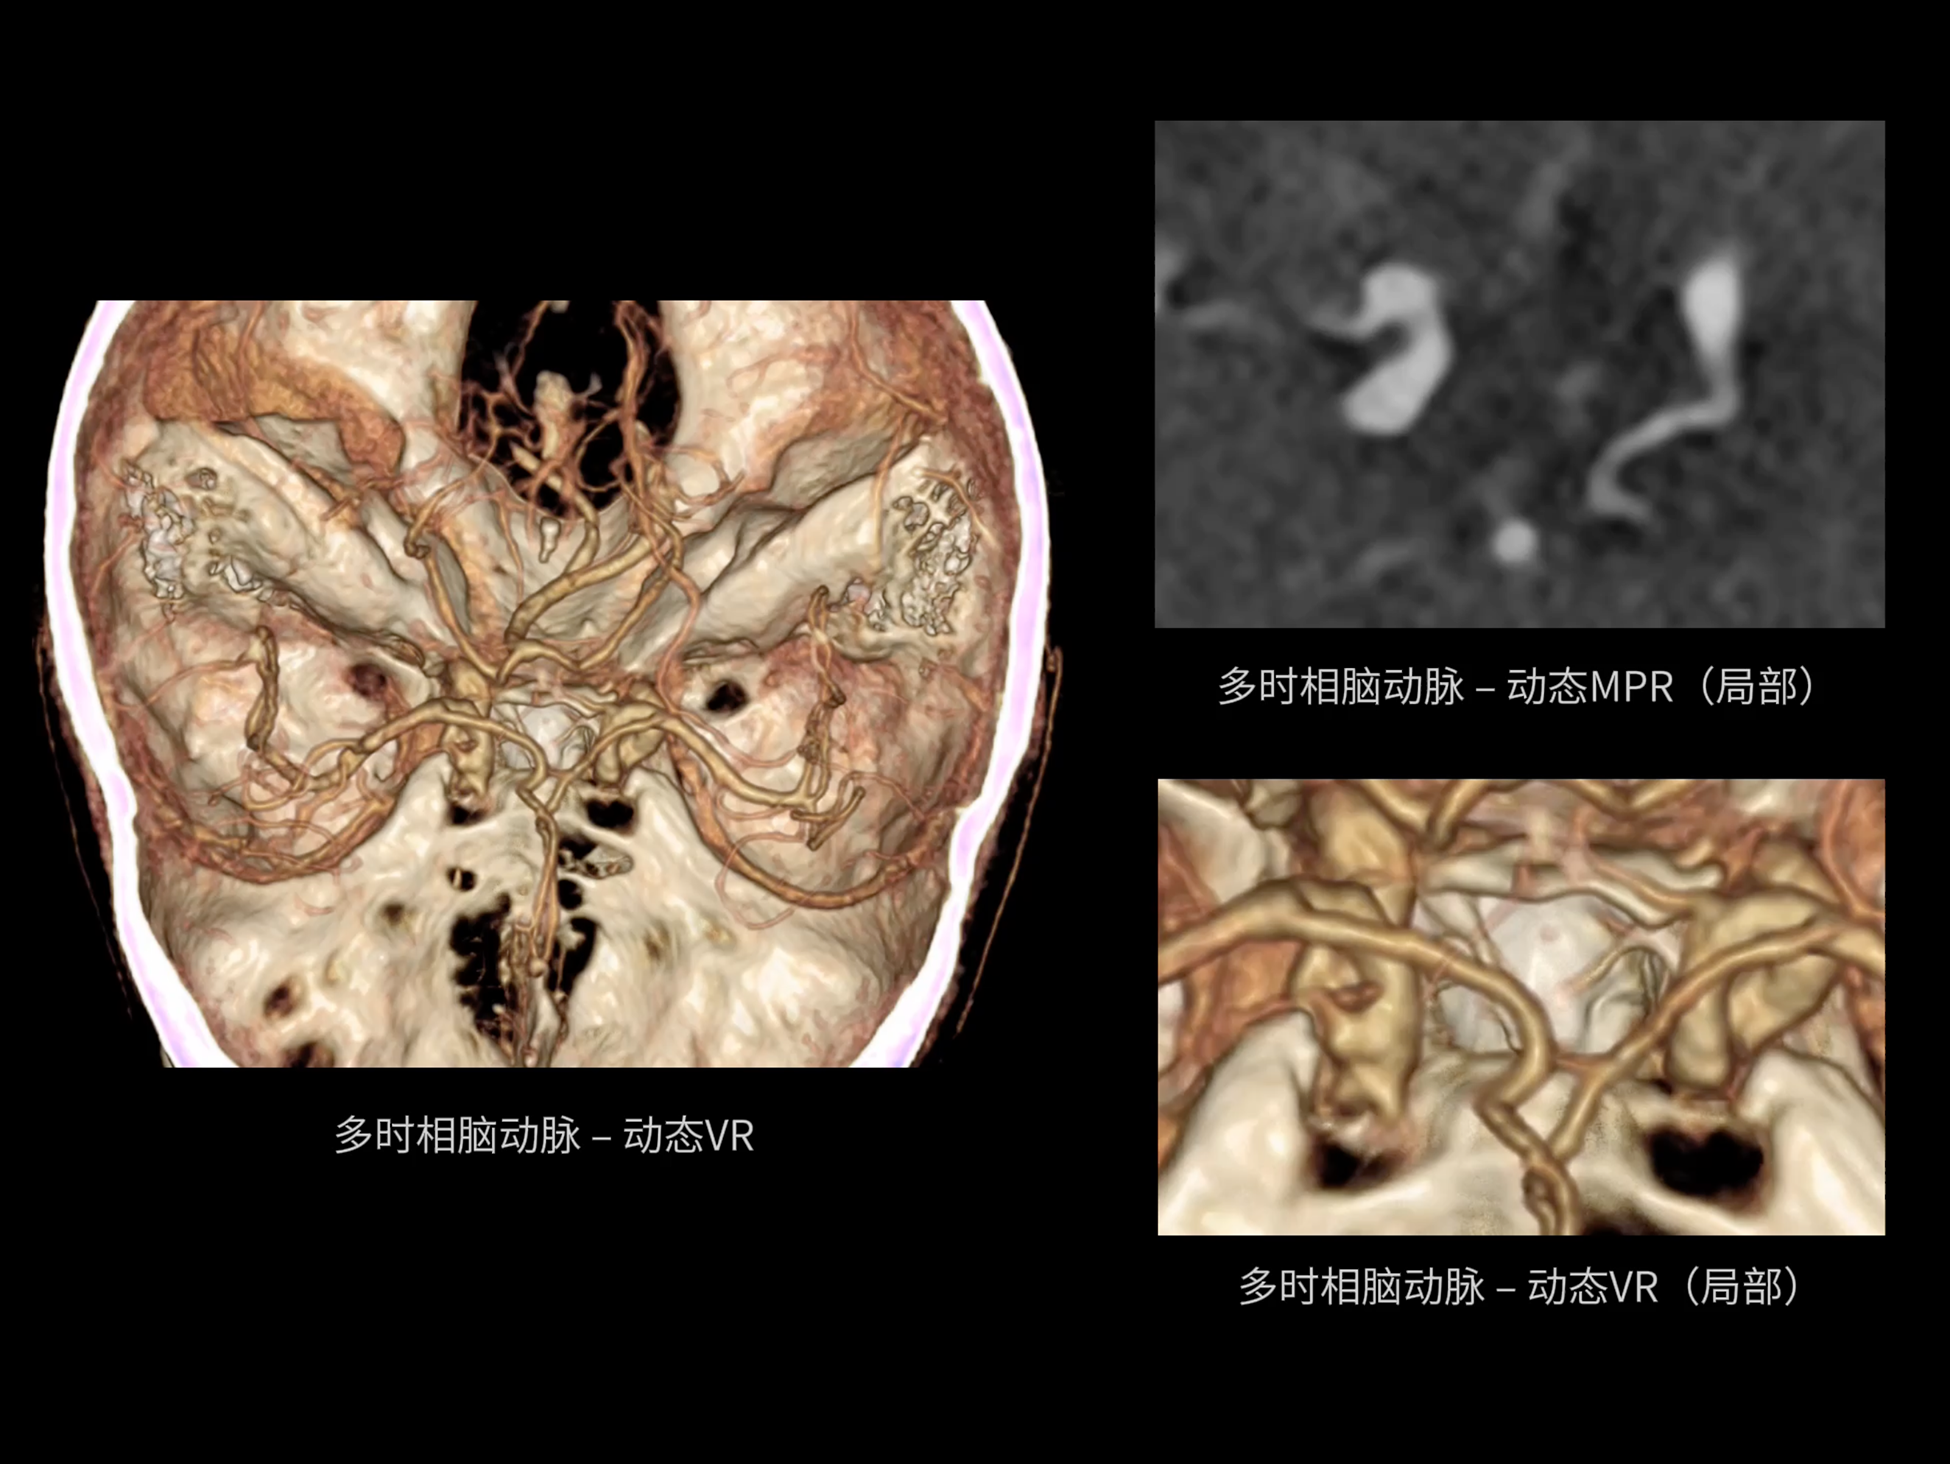

uCT SiriuX® 以全新双宽体系统架构,同步实现超高时间分辨率与宽体容积覆盖兼得,全面释放性能潜能,敏锐捕捉人体生理运动全景,带来动态影像新视角。

巅峰系统形态

双宽体“零”噪声时空探测器,Z 方向覆盖达16 cm,单圈即可完整扫描头颅、心脏等关键器官,结合超高时间分辨率,可实现真正意义上的全身各部位高清动态成像,让每一次扫描都更高效、更精准。

uCT SiriuX® 以16cm超宽Z轴覆盖,使超高时间分辨率应用于完整器官成像。无论是心脏搏动还是关节运动,整个目标区域可在同一瞬时被完整、清晰地捕捉,彻底消除时序误差,实现从“局部瞬间”到“全器官瞬时”的成像跨越。

瞬息捕捉

全器官同步

全身各部位动态CT成像